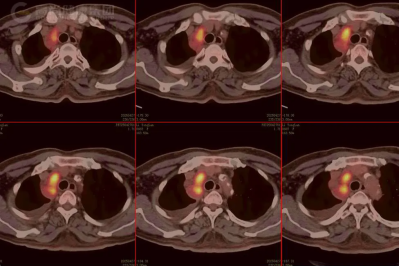

18F-FDG PET/CT 显像在乳腺外 Paget 病诊疗中的关键作用